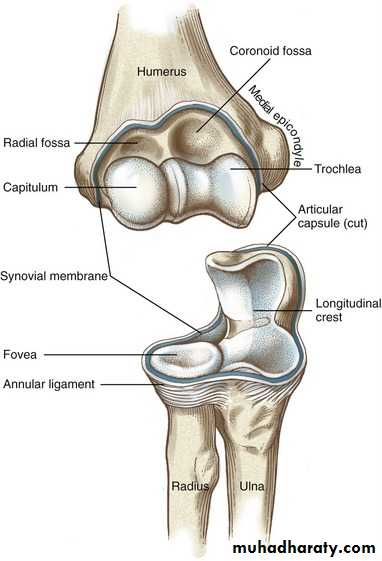

Cubitus valguscubitus is the Latin word for elbow and valgus means angled outward

DefinitionA deformity of the elbow that resulting in an increased carrying angle. (so that, with the arm extended at the side and the palm facing forward, the forearm and hand are held at greater than 15 degrees).

Cubitus valgus can be due to

1) congenital malformation, as in Turn syndrome and Noonan syndrome,2)Fracture ( non united fr. of the lateral humeral condyle )

Cubitus Varus

common deformity means a deformity of a limb in which its distal part is deviated towards the midline of the body . ( extended forearm is deviated towards midline of the body).Cubitus varus is often referred to as 'Gunstock deformity', due to the crooked nature of the healing

A common cause is the supracondylar fracture of humerus. It can be corrected via an osteotomy of the lower humerus fixed eithert externally or internally until bone heal.